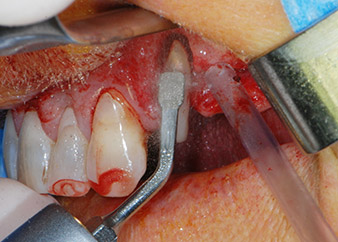

One month later, on the day of surgery, pain and inflammation at tooth 24 were minimal, but mobility of Miller class 2 was still present. After opening the flaps and cleaning the periapical and peri radicular infected tissue, the extent of the bone defect became obvious (Figs. 2 and 3).

At the buccal root, all vestibular and distal bone was missing. Attachment was essentially restricted to the palatal root, underlining the preliminary poor prognosis. Tooth 27 also showed a reduced horizontal attachment and a minimal apical rarefaction (cf. Fig. 1) without clinical symptoms.

Fig. 2 and 3: After raising flaps, one month after endodontic revision and initiation of full-mouth periodontal therapy, the buccal root of tooth 24 showed a total loss of bone and attachment.

However, we maintained our initial plan to retain both teeth as temporary bridge abutments during the six-months osseointegration period of the implants. At reentry, the situation would have to be reassessed. First, in an attempt to manage the endo-perio problem, the remaining root surface was carefully debrided with piezoelectric equipment (Piezomed, W&H, used with the spatula-shaped insert S1, originally designed for erosion of the lateral sinus wall) (Fig. 4).